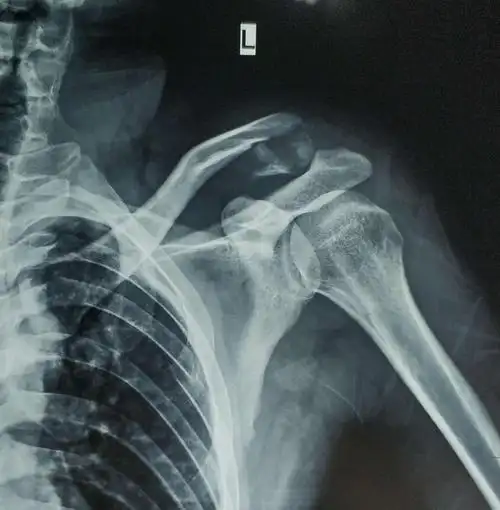

术前左锁骨x线片